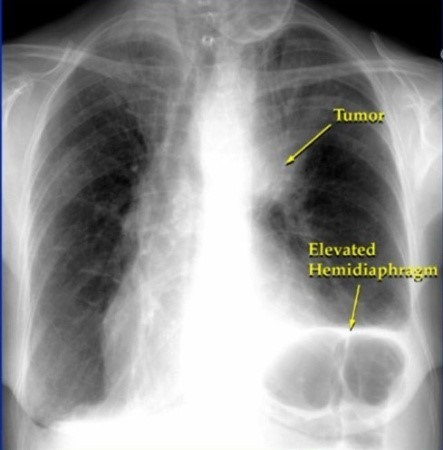

폐암 증상에는 기침, 체중 감소 흉통, 혈담 즉 피가 섞인 가래, 호흡곤란 등이 있지만, 위 증상은 다른 폐 질환에서도 나타날 수 있는 증상으로 구분하기가 어렵다. 그리고 폐암 초기에는 특별한 증상이 없는 경우가 대부분이라서 최근 흡연뿐 아니라 미세먼지 등 여러가지 요인으로 폐암이 발생하는 경우가 많아 정기검진으로 조기에 발견하는 것이 중요며 폐암 검진을 위해서는 특히나 저선량 흉부 CT를 촬영하는 것이 좋다라고 전문가들은 말하고 있습니다..

보통 숨소리는 크게 들리지 않지만, 목이나 폐 부분에 뭐가 걸린 느낌이 나듯이 숨소리가 거칠어지는 걸 느낍니다.면 폐에 문제가 생겼을 확률이 높다. 꼭 내원해 엑스레이를 촬영해 보는 게 바람직합니다..